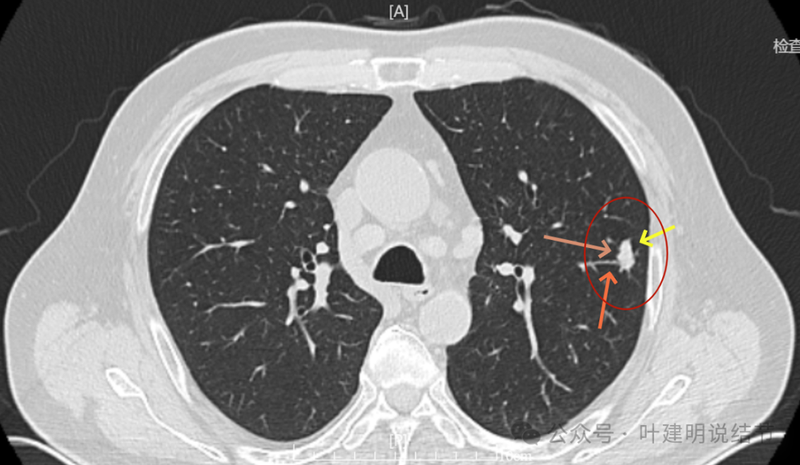

纵隔窗见为实性密度,同时见右侧纵隔腔静脉旁明显肿大淋巴结(蓝色箭头)。

回顾2023年右侧纵隔肿大淋巴结也是有的,而且大小与2024年9月的相仿。

上图是2024年9月的,隆突下也有肿大淋巴结。